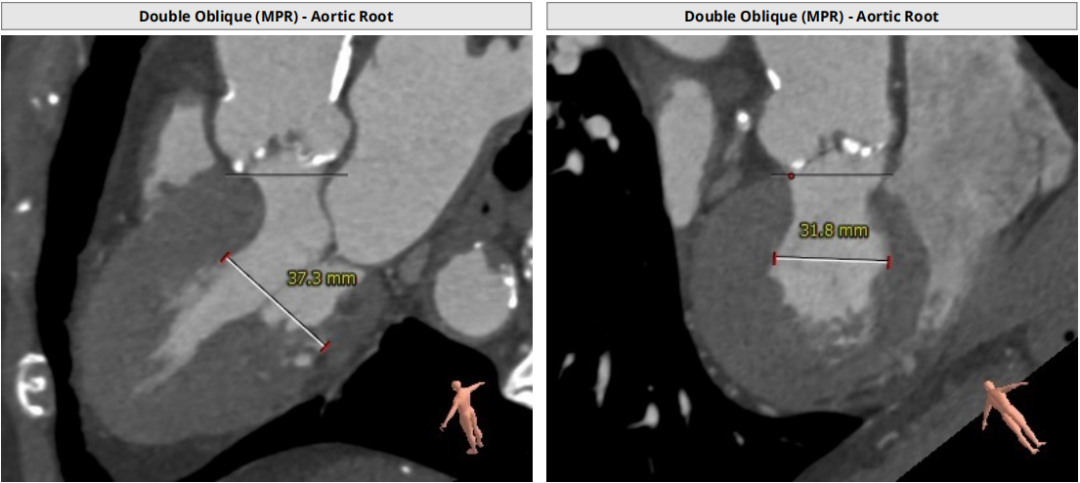

根部CT

三叶瓣,重度钙化,钙化主要分布在瓣叶游离缘,法式窦结构较大,双冠高度较高,升主动脉未见明显扩张,心脏角度40°,左室大小可,心肌肥厚,主动脉弓部走行较平缓,主动脉弓部可见钙化,过弓轻柔谨慎,以右侧股动脉为主入路。

唐熠达教授团队对病例进行多学科综合分析评估决定行一站式PCI+TAVI手术,结合患者91岁高龄,主动脉根部结构及双侧劲动脉粥样硬化斑块形成,脑动脉硬化情况采用20mm球囊预扩,拟植入VenusA-Valve L26瓣膜。